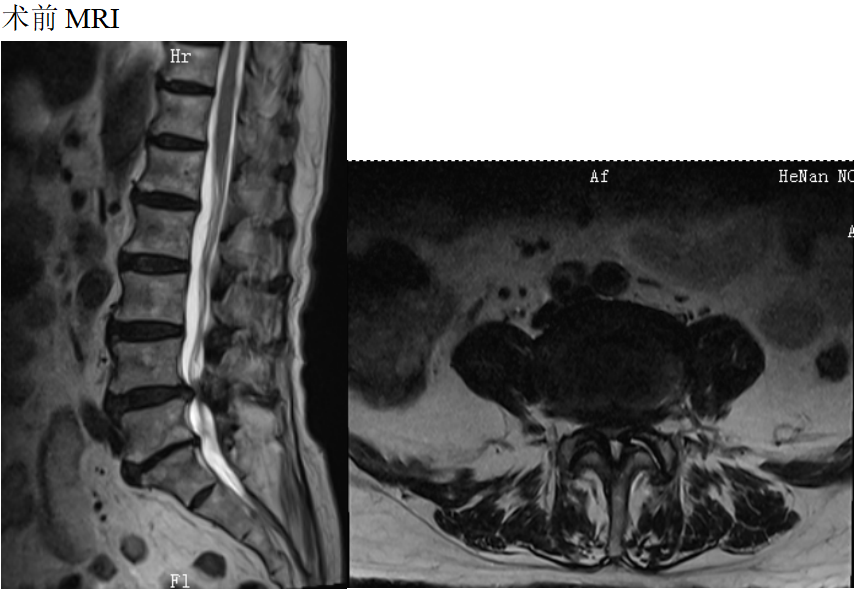

患者女性78岁,主诉:双下肢酸困麻木1年

现病史:1年前出现双下肢酸困麻木,以右侧为主,行走及站立时症状加重,平卧休息稍减轻,未治疗,上述症状持续加重,步行困难,步行能力约100米,为求诊治,现来我院,遂以“腰椎管狭窄症”为诊断收住我科。发病以来,饮食正常,睡眠一般,体力正常,大小便正常。